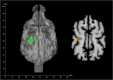

The dog rhinarium (naked and often moist skin on the nose-tip) is prominent and richly innervated, suggesting a sensory function. Compared to nose-tips of herbivorous artio- and perissodactyla, carnivoran rhinaria are considerably colder. We hypothesized that this coldness makes the dog rhinarium particularly sensitive to radiating heat. We trained three dogs to distinguish between two distant objects based on radiating heat; the neutral object was about ambient temperature, the warm object was about the same surface temperature as a furry mammal. In addition, we employed functional magnetic resonance imaging on 13 awake dogs, comparing the responses to heat stimuli of about the same temperatures as in the behavioural experiment. The warm stimulus elicited increased neural response in the left somatosensory association cortex. Our results demonstrate a hitherto undiscovered sensory modality in a carnivoran species.